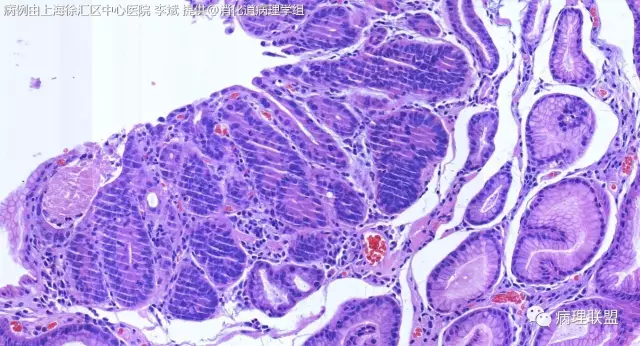

F-56 胃窦粘膜活检(低级别 vs 高级别)

女,56岁,胃窦粘膜活检(病例由上海徐汇区中心医院 李斌 提供,致谢!)

@李斌,高级别,腺体结构乱复杂,核异型性大,极向乱

@左淑英 子宫内膜受激素周期影响,腺体结构和上皮变化比较大,消化道受损伤、炎症等影响比较大,同样要看结构、看细胞,但标准确实不大一样。虽然具体病例需要具体分析,但我感觉在胃肠道,对于判断时感觉模棱两可的病例,表面成熟现象是区分反应性增生和低级别异型时可重复性相对比较好的指标;核极向是区分高低级别异型增生时可重复性相对比较好的指标。供参考